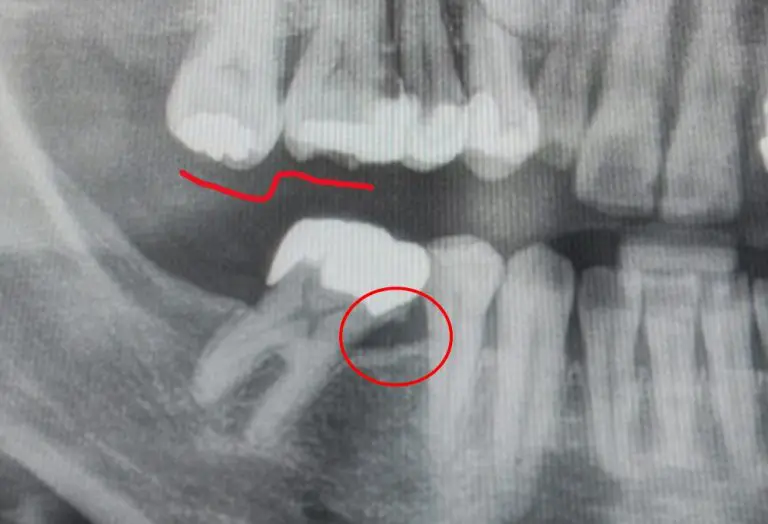

右下大臼歯は1歯欠損しているため、空いているスペースに歯牙が倒れこんでいます。

倒れている側は患者様ご自身による歯面の清掃が困難で、大きな歯石が付着していました(画像の赤丸部分)。

また、上顎の最後方臼歯は噛み合っていないため下に向かって挺出(ていしゅつ)※1してきています(画像赤線部分)。

画像はすでに歯を起こしている途中のレントゲン画像です。

初診時よりだいぶ歯が起きてきているのが分かります。

歯根の移動により新たな骨添加(成長)が見られます(赤丸部分)。